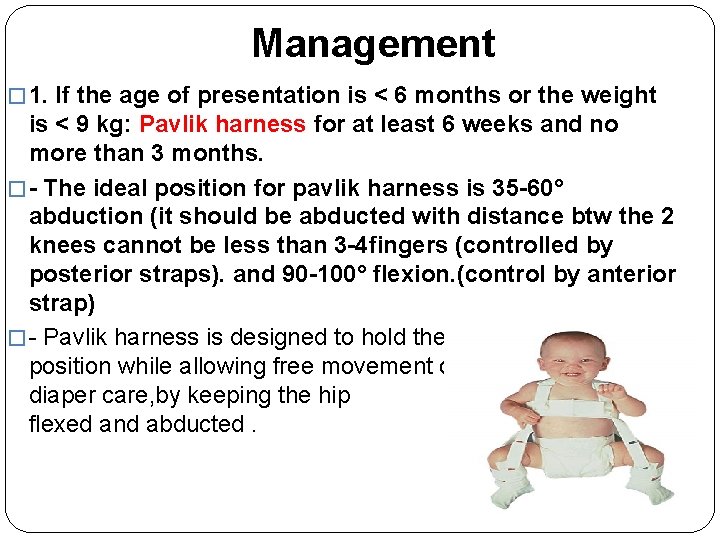

Management � 1. If the age of presentation is < 6 months or the weight is < 9 kg: Pavlik harness for at least 6 weeks and no more than 3 months. � - The ideal position for pavlik harness is 35 -60° abduction (it should be abducted with distance btw the 2 knees cannot be less than 3 -4 fingers (controlled by posterior straps). and 90 -100° flexion. (control by anterior strap) � - Pavlik harness is designed to hold the hip in the proper position while allowing free movement of the legs and easy diaper care, by keeping the hip flexed and abducted.